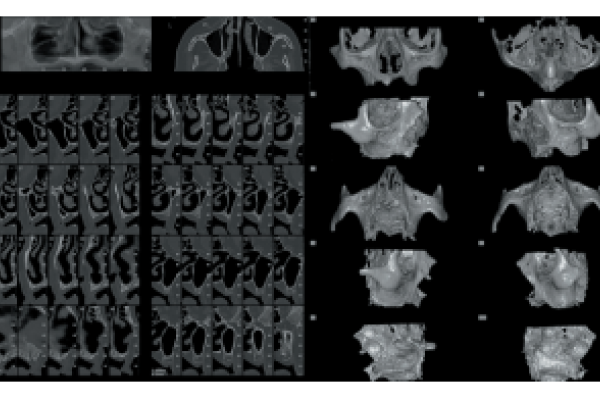

Retención de segundos molares mandibulares: evaluación mediante CBCT y consideraciones terapéuticas ante un caso clínico